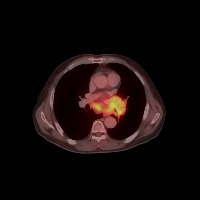

Diagnostic Aid in Medical Imaging: Radiologists could use this model to identify and characterize lymph node tumors in CT scans, assisting in early detection and diagnosis of potential cancerous growths.

Medical Research: Researchers might employ the model to study the characteristics and progressions of various types of lymph node tumors, towards producing more effective treatments and prevention strategies.

Training Medical Students: This model could serve as an invaluable tool for training medical students or residents in radiology, allowing them to familiarize themselves with the appearance and location of different lymph nodes, as well as to recognize varied tumor classifications.

Telemedicine: In remote or rural areas lacking immediate access to expert radiologists, this model can come handy as it assists primary care providers or mid-level practitioners in identifying lymph node tumors and making more effective referrals.

Second Opinion: Patients with possible lymph node tumors might use the model as a 'second opinion' to verify diagnoses, ensuring there are no oversights in their scans.